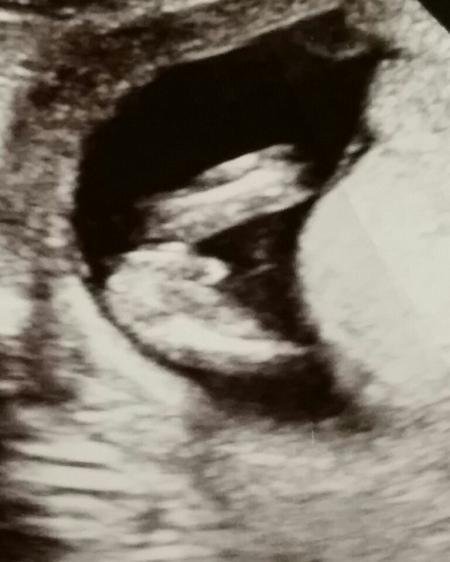

Hallo ihr Lieben! Bin in der 15 Woche und mein Frauenarzt hat auf mein Bitten hin mal zwischen die Füße geschallt. :-) Was wurde ihr sagen? Liebe Grüße

Er tippt auf einen Jungen....ist aber natürlich noch sehr früh. Aber nach 3 Mädchen erwarten wir jetzt unser letztes Wunschkind und sind natürlich total aufgeregt. :-)